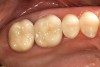

A patient presented with large amalgam restorations and recurrent caries on teeth Nos. 2 and 3 (Figure 2). After reviewing the treatment options, the patient chose all-ceramic crowns to restore the teeth. The specific all-ceramic crowns selected for the case were zirconia crowns. After completion of the crown preparations, soft-tissue retraction was achieved and the tooth surfaces were cleaned and dried (Figure 3). The teeth and soft tissues were isolated and lightly sprayed with a titanium-dioxide powder to create a reflective surface (). The powder provides contrast points for scanning to enhance recording the 3-D models and to improve the speed of recording.

Figure 3  Gingival tissues have been retracted with cord in readiness for the digital impression.

Figure 3